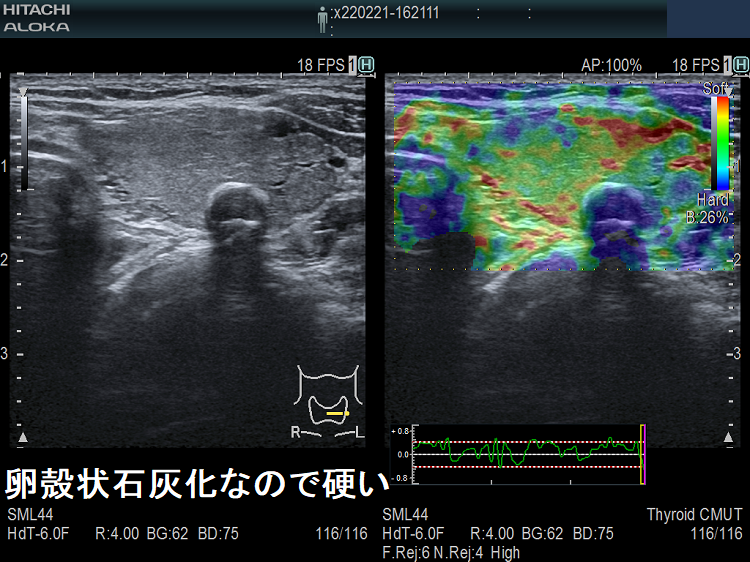

被膜が石灰化した腫瘍

被膜が石灰化した腫瘍は、プローブによる用手圧迫の歪が石灰化被膜で打ち消されるためエラストグラフィーは無効です。